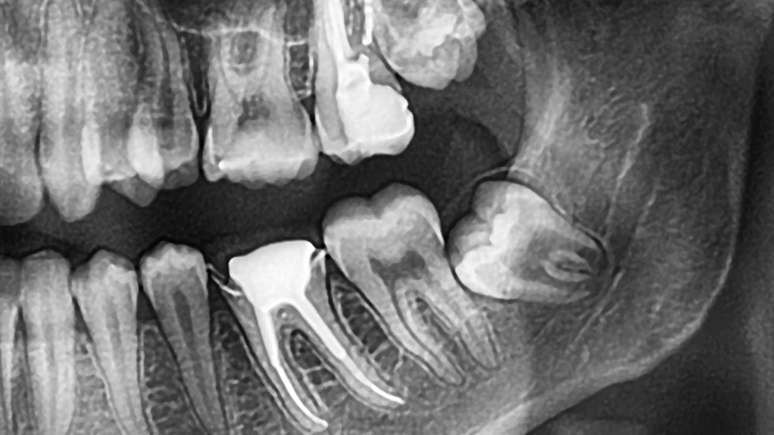

Na maioria das vezes, o siso fica sem espaço para erupcionar e começa a pressionar os dentes vizinhos, alterando o alinhamento do sorriso e causando dor ou inflamação. Em casos em que o dente fica parcialmente exposto (os chamados semi-inclusos), há maior risco de acúmulo de resíduos e infecções. Os sintomas mais comuns incluem dor intensa, inchaço, sensibilidade e até fragilidade óssea. Por isso, a extração costuma ser o tratamento mais indicado.

A cirurgia de remoção do siso é simples, feita com anestesia local e duração média de menos de uma hora. O paciente tem alta no mesmo dia e deve seguir recomendações básicas: repouso, alimentação leve e boa higiene bucal. O ideal é consultar o dentista antes que os sisos causem desconforto. Com exames de imagem, o profissional consegue identificar se o dente está em formação e avaliar o momento certo para agir - muitas vezes, de forma preventiva.